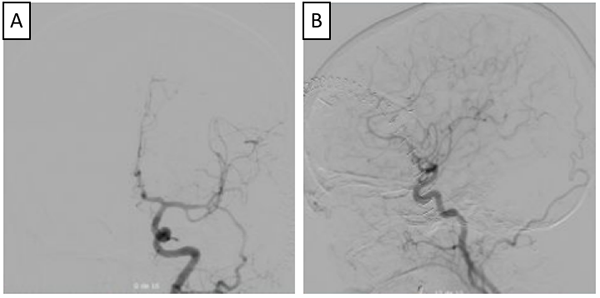

Luego del análisis del caso, y teniendo en cuenta la presencia del trombo intracavitario, el cuello del aneurisma, la posición favorable del saco aneurismático, y la edad de la paciente, se decidió que la cirugía era la mejor opción terapéutica, se realizó una craneotomía pterional derecha, y un abordaje transilviano bajo visión microscópica. Se encontró un aneurisma de gran tamaño dependiente de la AcomA (Figura 2), con dirección anteroinferior, calcificación en las paredes del domo y signos de trombosis. Una vez se identificó el cuello, y ambas A1 y A2, se posicionó un clip recto de 9 mm, que luego se reacomodó con otro clip definitivo de 9 mm, se retiró el previamente colocado, quedando con un solo clip definitivo. A continuación se comprobó la permeabilidad de los vasos A1 y A2, así como de la arteria recurrente de Heubner ipsilateral con doppler intraoperatorio. Se procedió con la disección del domo del aneurisma y trombectomía con aspirador ultrasónico, dejando el interior del aneurisma friable, y descomprimiendo de esta manera el nervio y el quiasma óptico. El procedimiento finalizó sin complicaciones, la paciente mejoró del déficit en el postoperatorio inmediato, y se llevó a arteriografía de control al día siguiente de la intervención, con la que se confirmó el adecuado clipaje de la lesión (Figura 3).

Figura 3. Arteriografía de control postoperatoria (A y B), en la que se observa adecuada exclusión de aneurisma cerebral